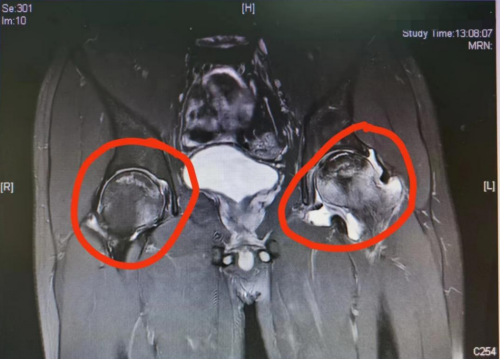

标记处为股骨头坏死磁共振下表现

“外伤、酒精、激素等都是引起股骨头坏死的常见病因。”余敏告诉叶戎,长期大量饮酒,会损伤血管内皮细胞,导致血管痉挛,影响股骨头的血供减少,久而久之,就会引起股骨头缺血坏死。